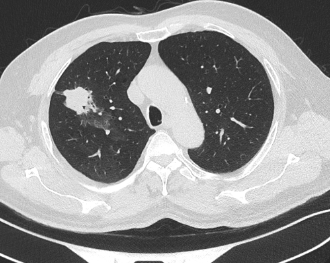

近日,昭通市中医医院呼吸与危重症医学科二科成功为一名合并多种基础疾病的61岁肺癌患者实施了昭通首例经口支气管镜超声(EBUS)引导下肺癌冷冻消融术。该患者因“反复咳嗽、咳痰1年,确诊右肺鳞癌2月余”入院。胸部增强CT显示其右肺上叶存在两个高危结节(Lung-RADs 4X类),同时合并慢性支气管炎伴肺气肿、肺炎、冠心病(支架术后)、肺大疱、肺不张等疾患。

术前患者CT